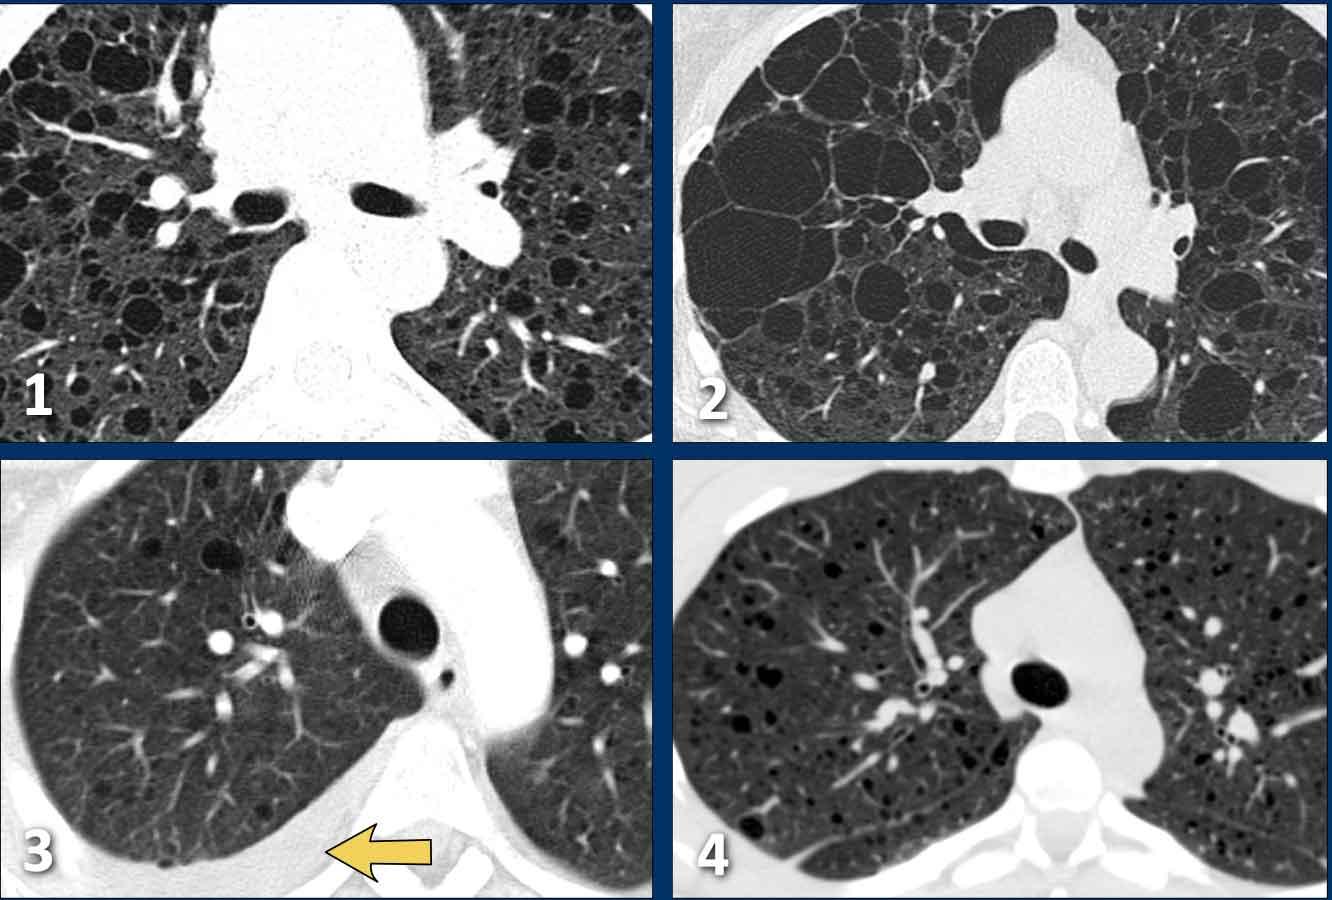

Tổn thương đa ổ

Khi có nhiều hình ảnh trông giống nang, cần phân biệt bệnh phổi dạng nang thực sự với các bệnh lý bắt chước khác (hình minh họa).

- Nhiều nang phổi với thành mỏng ở bệnh nhân LCH giai đoạn tiến triển. Đây là bệnh phổi dạng nang thực sự.

- Khí phế thũng trung tiểu thùy, biểu hiện là các lỗ đen không có thành. Lưu ý dấu hiệu chấm trung tâm (mũi tên). Khí phế thũng có thể là yếu tố gây nhầm lẫn thực sự và sẽ được thảo luận chi tiết hơn ở phần sau.

- Tổ ong (Honeycombing) biểu hiện là chồng các nang thành dày ở ngoại vi thùy dưới ở bệnh nhân xơ phổi.

- Giãn phế quản dạng nang, biểu hiện là các ống dạng nang. Thường không khó phân biệt khi cuộn qua các lát cắt, nhưng đôi khi có thể gây thách thức.